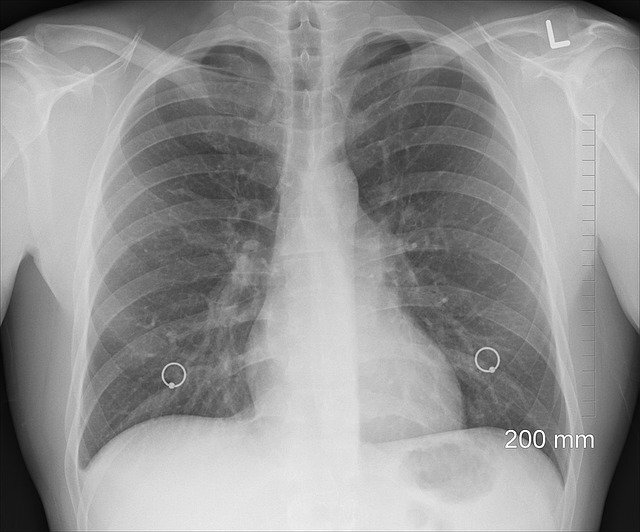

Сигаретный дым вызывает бурный воспалительный ответ в легких, отмечает профессор. «Самая популярная проблема курильщиков — ХОБЛ (хроническая обструктивная болезнь легких). Это заболевание, которое возникает от вдыхания никотина, его суррогатов и других вредных веществ, находящихся в воздухе. При ХОБЛ сужаются просветы бронхов и человек не может нормально дышать, снижаются эластичные функции легких, возникает чрезмерная воздушность (гиперинфляция легких), повышается продукция слизи, возникают трудности ее отхождения», — говорит Аркадий Верткин. В дальнейшем развивается легочно-сердечная недостаточность (легочное сердце).

ХОБЛ можно заподозрить и без особенной диагностики. Вот основные симптомы болезни:

одышка;

кашель с мокротой (чаще утром и днем, чем ночью);

на расстоянии слышны свистящие хрипы;

появляется дыхание сквозь сомкнутые губы.